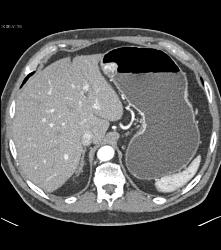

Glomus Tumor